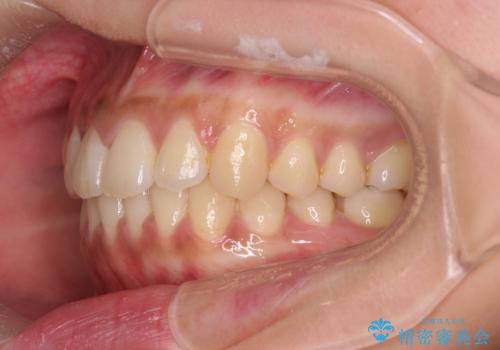

前歯のがたつきをすっきり マウスピース矯正

- 長年気になっていた前歯のがたつきをマウスピース矯正で治したい!と希望され来院されました。

奥歯の噛み合わせには問題がなく、前歯のがたつきの改善のみで十分に審美的な結果が得られるため、ワイヤーではなくマウスピース矯正での治療を計画します。

しっかりと前歯のがたつきは改善し見た目が大きく良くすることができました。